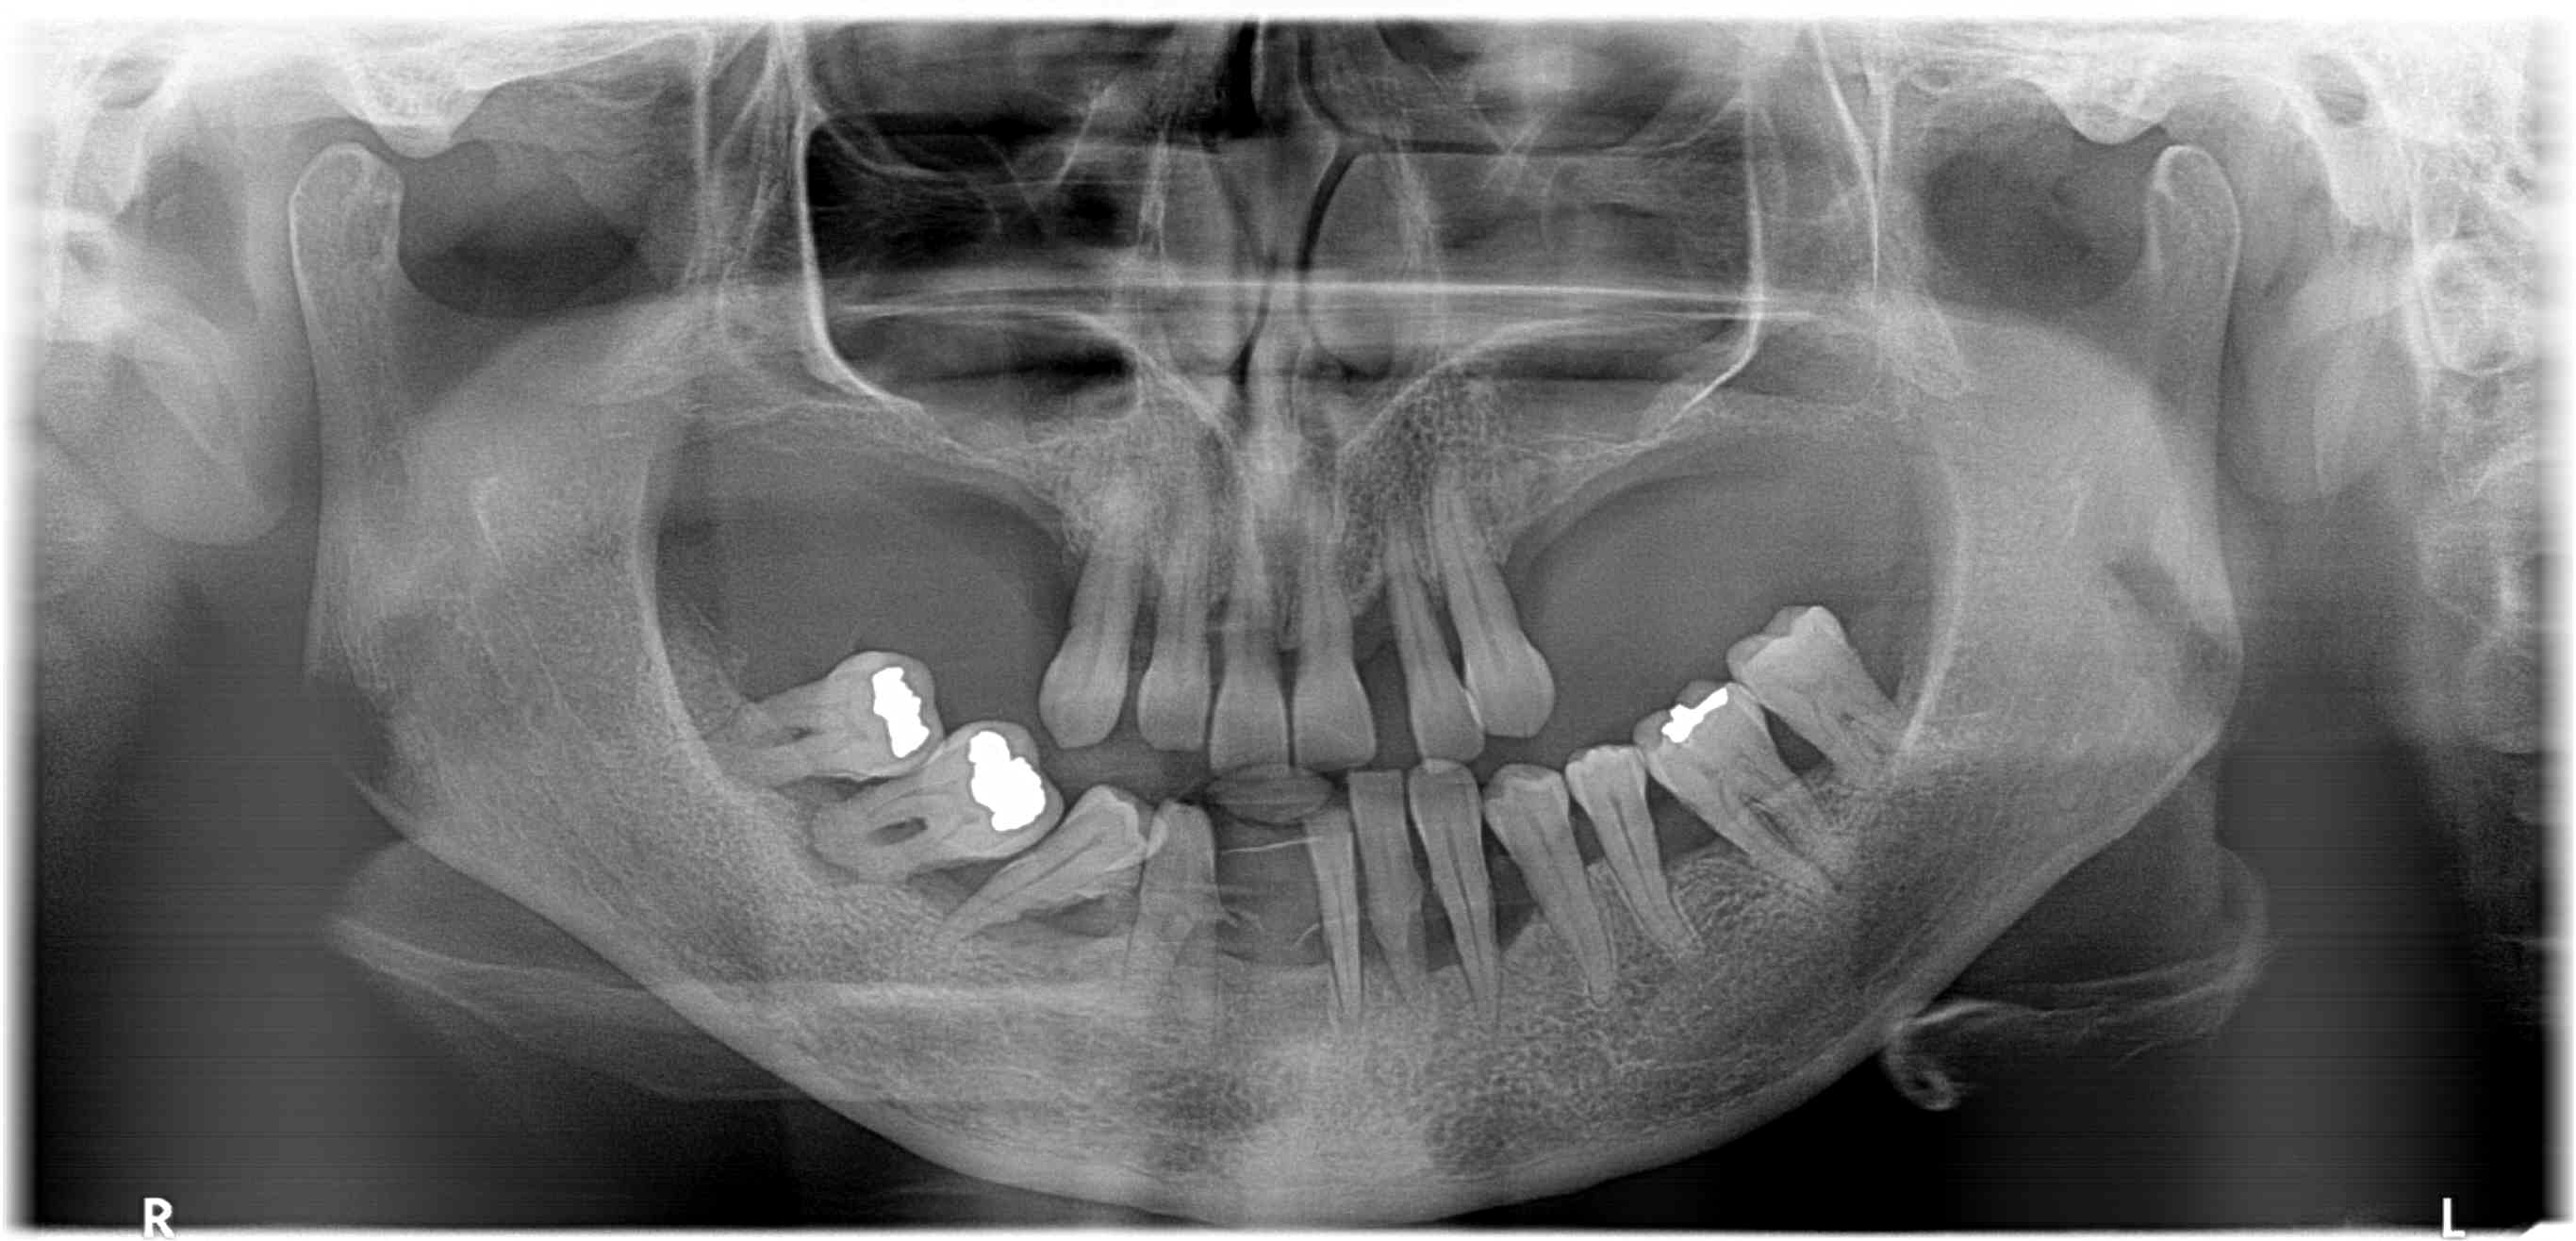

Fogív rendezés

A frontfogak torlódását és a harapás eltérését sikeresen korrigáltuk, így a fogív szabályossá vált, a rágófunkció javult és az esztétikai megjelenés is sokkal harmonikusabb lett.

Fogiv-rendezes-elott

Fogiv-rendezes-utan

Előtte

Utána